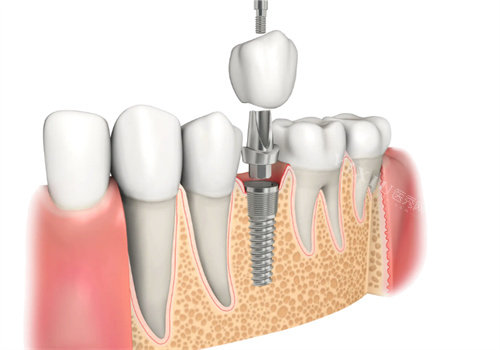

姜宝岐医生是山东省口腔医院种植中心的医师,拥有28年的临床经验。他擅长人工牙种植外科及修复特色,对于缺牙后的修复和全口牙缺失的修复有丰富的经验,能够为患者提供个性化的种植方案。

万金华医生是济南可恩口腔医院的种植牙医师,从业多年,技术娴熟。他精通多种种植牙技术,包括小创口种植牙、即刻种植牙等,能够根据患者的具体情况选择更适合的种植方式,让患者在种植过程中感受到更少的痛苦和更快的改善。

吴高义医生是济南联合博士口腔门诊部的种植牙医师,他经验充足,能够熟练掌握即刻种植牙、小创口种植牙、上颌窦提升等多种种植牙技术。他还擅长处理复杂的口腔问题,为患者提供高质量的种植牙服务。